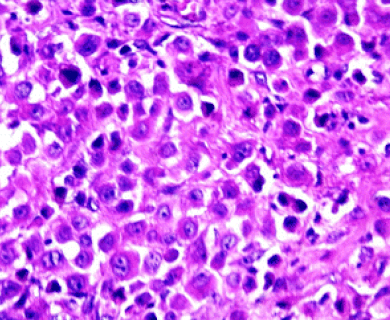

Pathologists look at tumor and tissue samples and determine what cells they can see. If the majority of cells from your mesothelioma sample are epithelioid cells, your mesothelioma subtype is determined to be epithelioid mesothelioma.

A tissue biopsy is the only way to diagnose epithelioid mesothelioma. This procedure involves taking samples of suspicious tissue. Pathologists examine the tissue samples under a microscope to identify specific cell characteristics.

Epithelioid mesothelioma cells clump together in groups and don’t tend to travel. These cell types are less likely to spread to other areas of the body. When a pathologist confirms the presence of specific cancer cells, an accurate diagnosis of your mesothelioma type can be made.

The tool or technique for studying cancer tissues is called immunohistochemistry. Pathologists look at stained samples, testing for certain proteins linked to epithelial cells. If pathologists find proteins from other cancers, they’ll rule out epithelioid mesothelioma.

The proteins that help doctors identify epithelioid mesothelioma from different types of cancer include: calretinin, D2-40, keratin 5/6, podoplanin and WT-1 protein. An official diagnosis depends on more than just immunohistochemistry. It also considers the tumor’s appearance, location and cell traits.

Epithelial subtype mesothelioma describes the type of cells the pathologist is seeing under the microscope when they look at a patient’s tumor.

While epithelioid is a subtype of mesothelioma, there are further subtypes of the epithelioid type. Pathologists can identify these cell subtypes with immunohistochemistry.